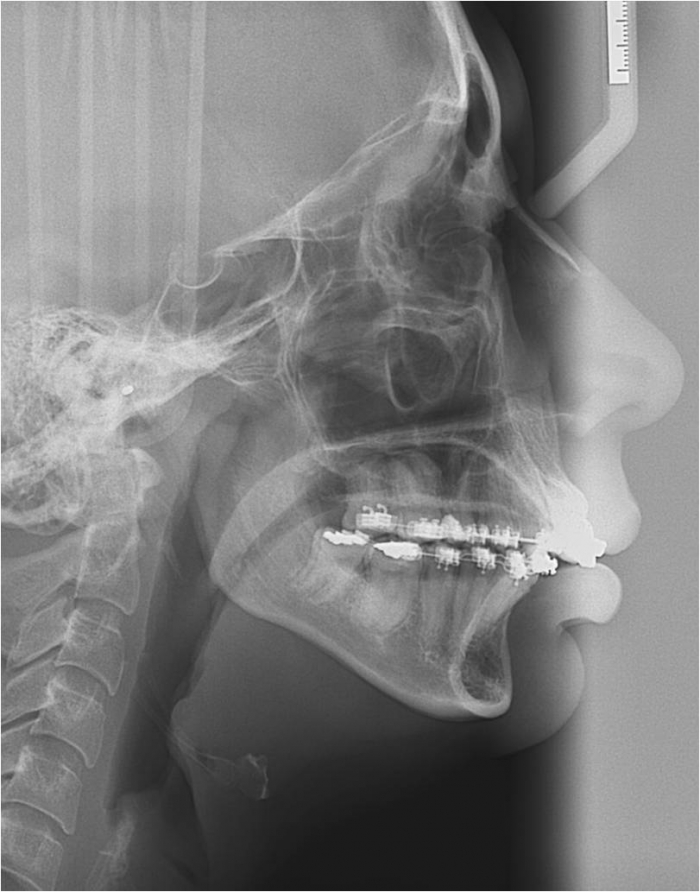

Telerradiografia inicial